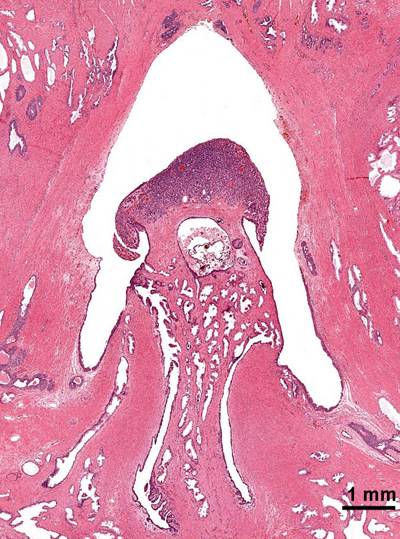

在周围神经系统内,若干条神经纤维构成一神经纤维束,外包数层扁平上皮样细胞组成的神经束膜。数个神经纤维束集中形成神经。每条神经纤维外包以网状疏松结缔组织构成的神经内膜。神经将神经中枢、感觉器官和效应器连结在一起。由感觉传入纤维组成的神经称感觉神经;由传送冲动至效应器的传出神经纤维组成的神经称为运动神经。大多数神经由感觉和运动两种纤维组成,而称为混合神经。